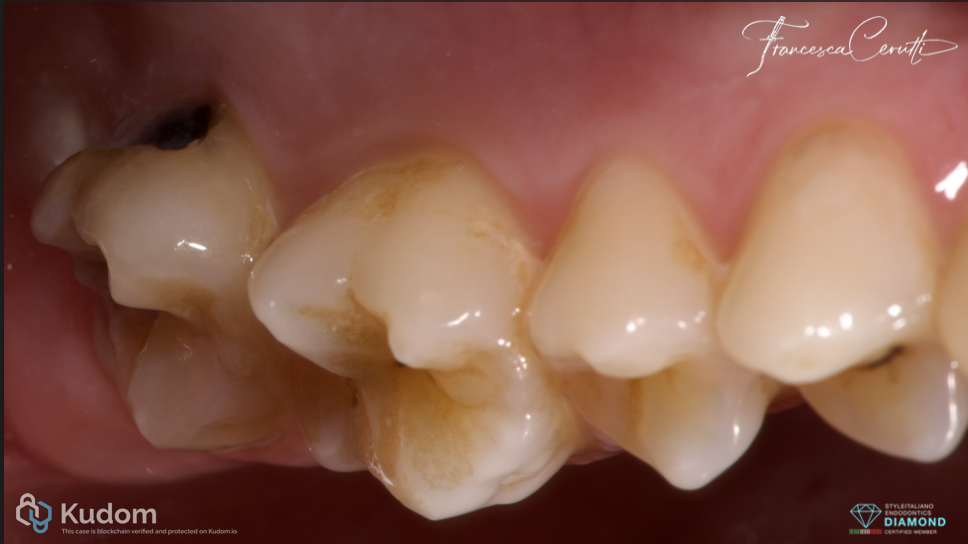

Fig. 1

A patient with symptomatic irreversible pulpitis came to my attention. A large buccal decay was the cause of the pathology.